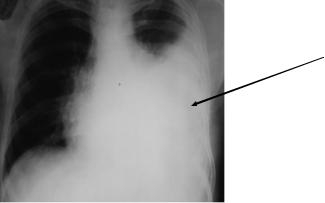

Рентгенологическое исследование. Наиболее ранние рентгенологические признаками плеврального выпота - тупой срезанный рѐберно-диафрагмальный угол и затенение задней части диафрагмы в боковой проекции. Необходимо помнить, что повышенная «плотность» при рентгенологическом исследовании часто принимается за паренхиматозный инфильтрат, хотя это может быть признаком наличия плевральной жидкости. При вертикальном положении больного свободная жидкость под действием силы тяжести перемещается в плевральной полости в задний реберно диафрагмальный синус. Прямая обзорная рентгенограмма может и не выявить патологии, если объѐм выпота менее 300 мл. Если задний реберно диафрагмальный синус затемнен или задняя часть диафрагмы не визуализируется на боковой рентгенограмме, для диагностики плевральной жидкости необходимо с обеих сторон провести рентгенографию в латеропозиции или провести ультразвуковое исследование. Если расстояние между грудной стенкой и легким менее 10 мм, плевральный выпот не является клинически значимым, и в этом случае будет трудно получить жидкость с помощью торакоцентеза. Если расстояние превышает 10 мм, необходимы исследования для установления причины плеврального выпота. В наружных отделах жидкости больше, поскольку лѐгкое поджато к корню, что приводит к появлению косой, а не горизонтальной границы тени (рис. 5-2). Отчѐтливый верхний горизонтальный уровень экссудата становится виден после проведения плевральной пункции (попадания газа в плевральную полость).

Рис. 5-2. Прямая рентгенограмма органов грудной полости : левосторонний экссудативный плеврит .